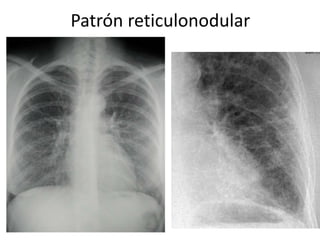

Patrón reticulonodular

Patrón reticular